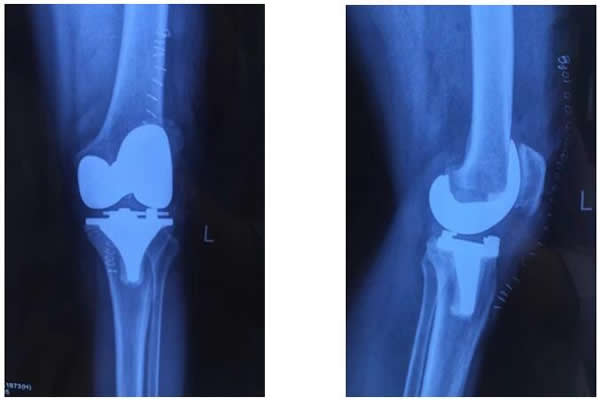

白奶奶今年72歲,雙膝關(guān)節(jié)疼痛10余年。近兩年來,雙膝疼痛加重,經(jīng)多方治療沒有任何效果,雙下肢也逐漸呈明顯的“O型腿”。近期疼痛加重,行走困難,這讓白奶奶的家人非常著急,為解除病痛,白奶奶一家慕名前來西電集團(tuán)醫(yī)院骨科就診。經(jīng)該院骨科張富軍主任詳細(xì)診查,雙膝拍片確診患有:雙膝關(guān)節(jié)骨性關(guān)節(jié)炎合并雙側(cè)內(nèi)翻屈曲畸形。為提高生活質(zhì)量,解除病痛,建議進(jìn)行同期雙膝人工關(guān)節(jié)置換手術(shù)。

術(shù)前,骨科主任張富軍、主治醫(yī)師張浩為患者制定了嚴(yán)格的治療方案,經(jīng)過2周的術(shù)前準(zhǔn)備感染指標(biāo)降至正常,于2017年1月13日在手術(shù)室、麻醉科等相關(guān)科室的周密配合下,由張富軍主任、張浩主治醫(yī)師、何鵬主治醫(yī)師、裴海波醫(yī)師為白奶奶進(jìn)行同期雙側(cè)人工膝關(guān)節(jié)表面置換手術(shù),麻醉由龐曉紅主任、劉文雄醫(yī)師擔(dān)任,手術(shù)順利,手術(shù)歷時(shí)2.5小時(shí),術(shù)后恢復(fù)滿意,術(shù)后第1天白奶奶已能下床行走,術(shù)后第6天行走出院,白奶奶對手術(shù)效果非常滿意并讓家人為骨科送來了錦旗表示感謝。

目前,西電醫(yī)院骨科治療骨關(guān)節(jié)炎進(jìn)行人工關(guān)節(jié)置換手術(shù)經(jīng)驗(yàn)巳經(jīng)非常成熟,以往對于七十周歲以上的患者往往一次只做一側(cè)。隨著我國老齡人口的不斷增加,高齡患者會(huì)越來越多,骨關(guān)節(jié)炎疾病影響老人生活質(zhì)量,對骨科醫(yī)生也是個(gè)新挑戰(zhàn)。近年來隨著骨科關(guān)節(jié)置換技術(shù)的不斷提高,關(guān)節(jié)置換手術(shù)的時(shí)間也大大縮短;同時(shí)對相應(yīng)的并發(fā)癥也有了一定的預(yù)防和處理能力,如氨甲環(huán)酸和利伐沙班等藥物的合理使用,在大幅度減少手術(shù)出血的同時(shí)也將深靜脈血栓形成的風(fēng)險(xiǎn)降到最低。采用國際快速康復(fù)理念,通過圍手術(shù)期制定個(gè)體化的鎮(zhèn)痛方案和康復(fù)鍛煉計(jì)劃,幫助患者在基本無痛的良好體驗(yàn)下盡快恢復(fù)關(guān)節(jié)功能。